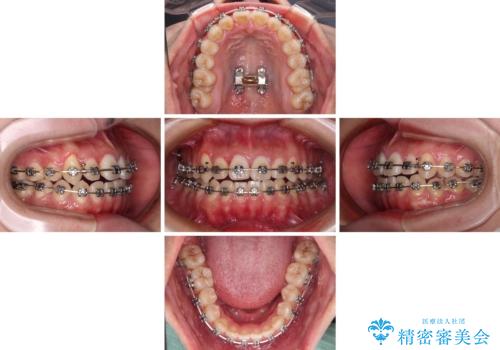

上顎歯列が狭窄していたため、急速拡大装置により上顎骨を側方に拡大し、その後ワイヤー装置にて矯正治療を行うこととしました。

上顎骨を拡大することで、八重歯やデコボコを歯列に収めることができ、下顎の歯が外に位置していた奥歯の咬み合わせも改善することができました。

スペースも短期間に獲得できるため、1年程度で治療を終えることができました。